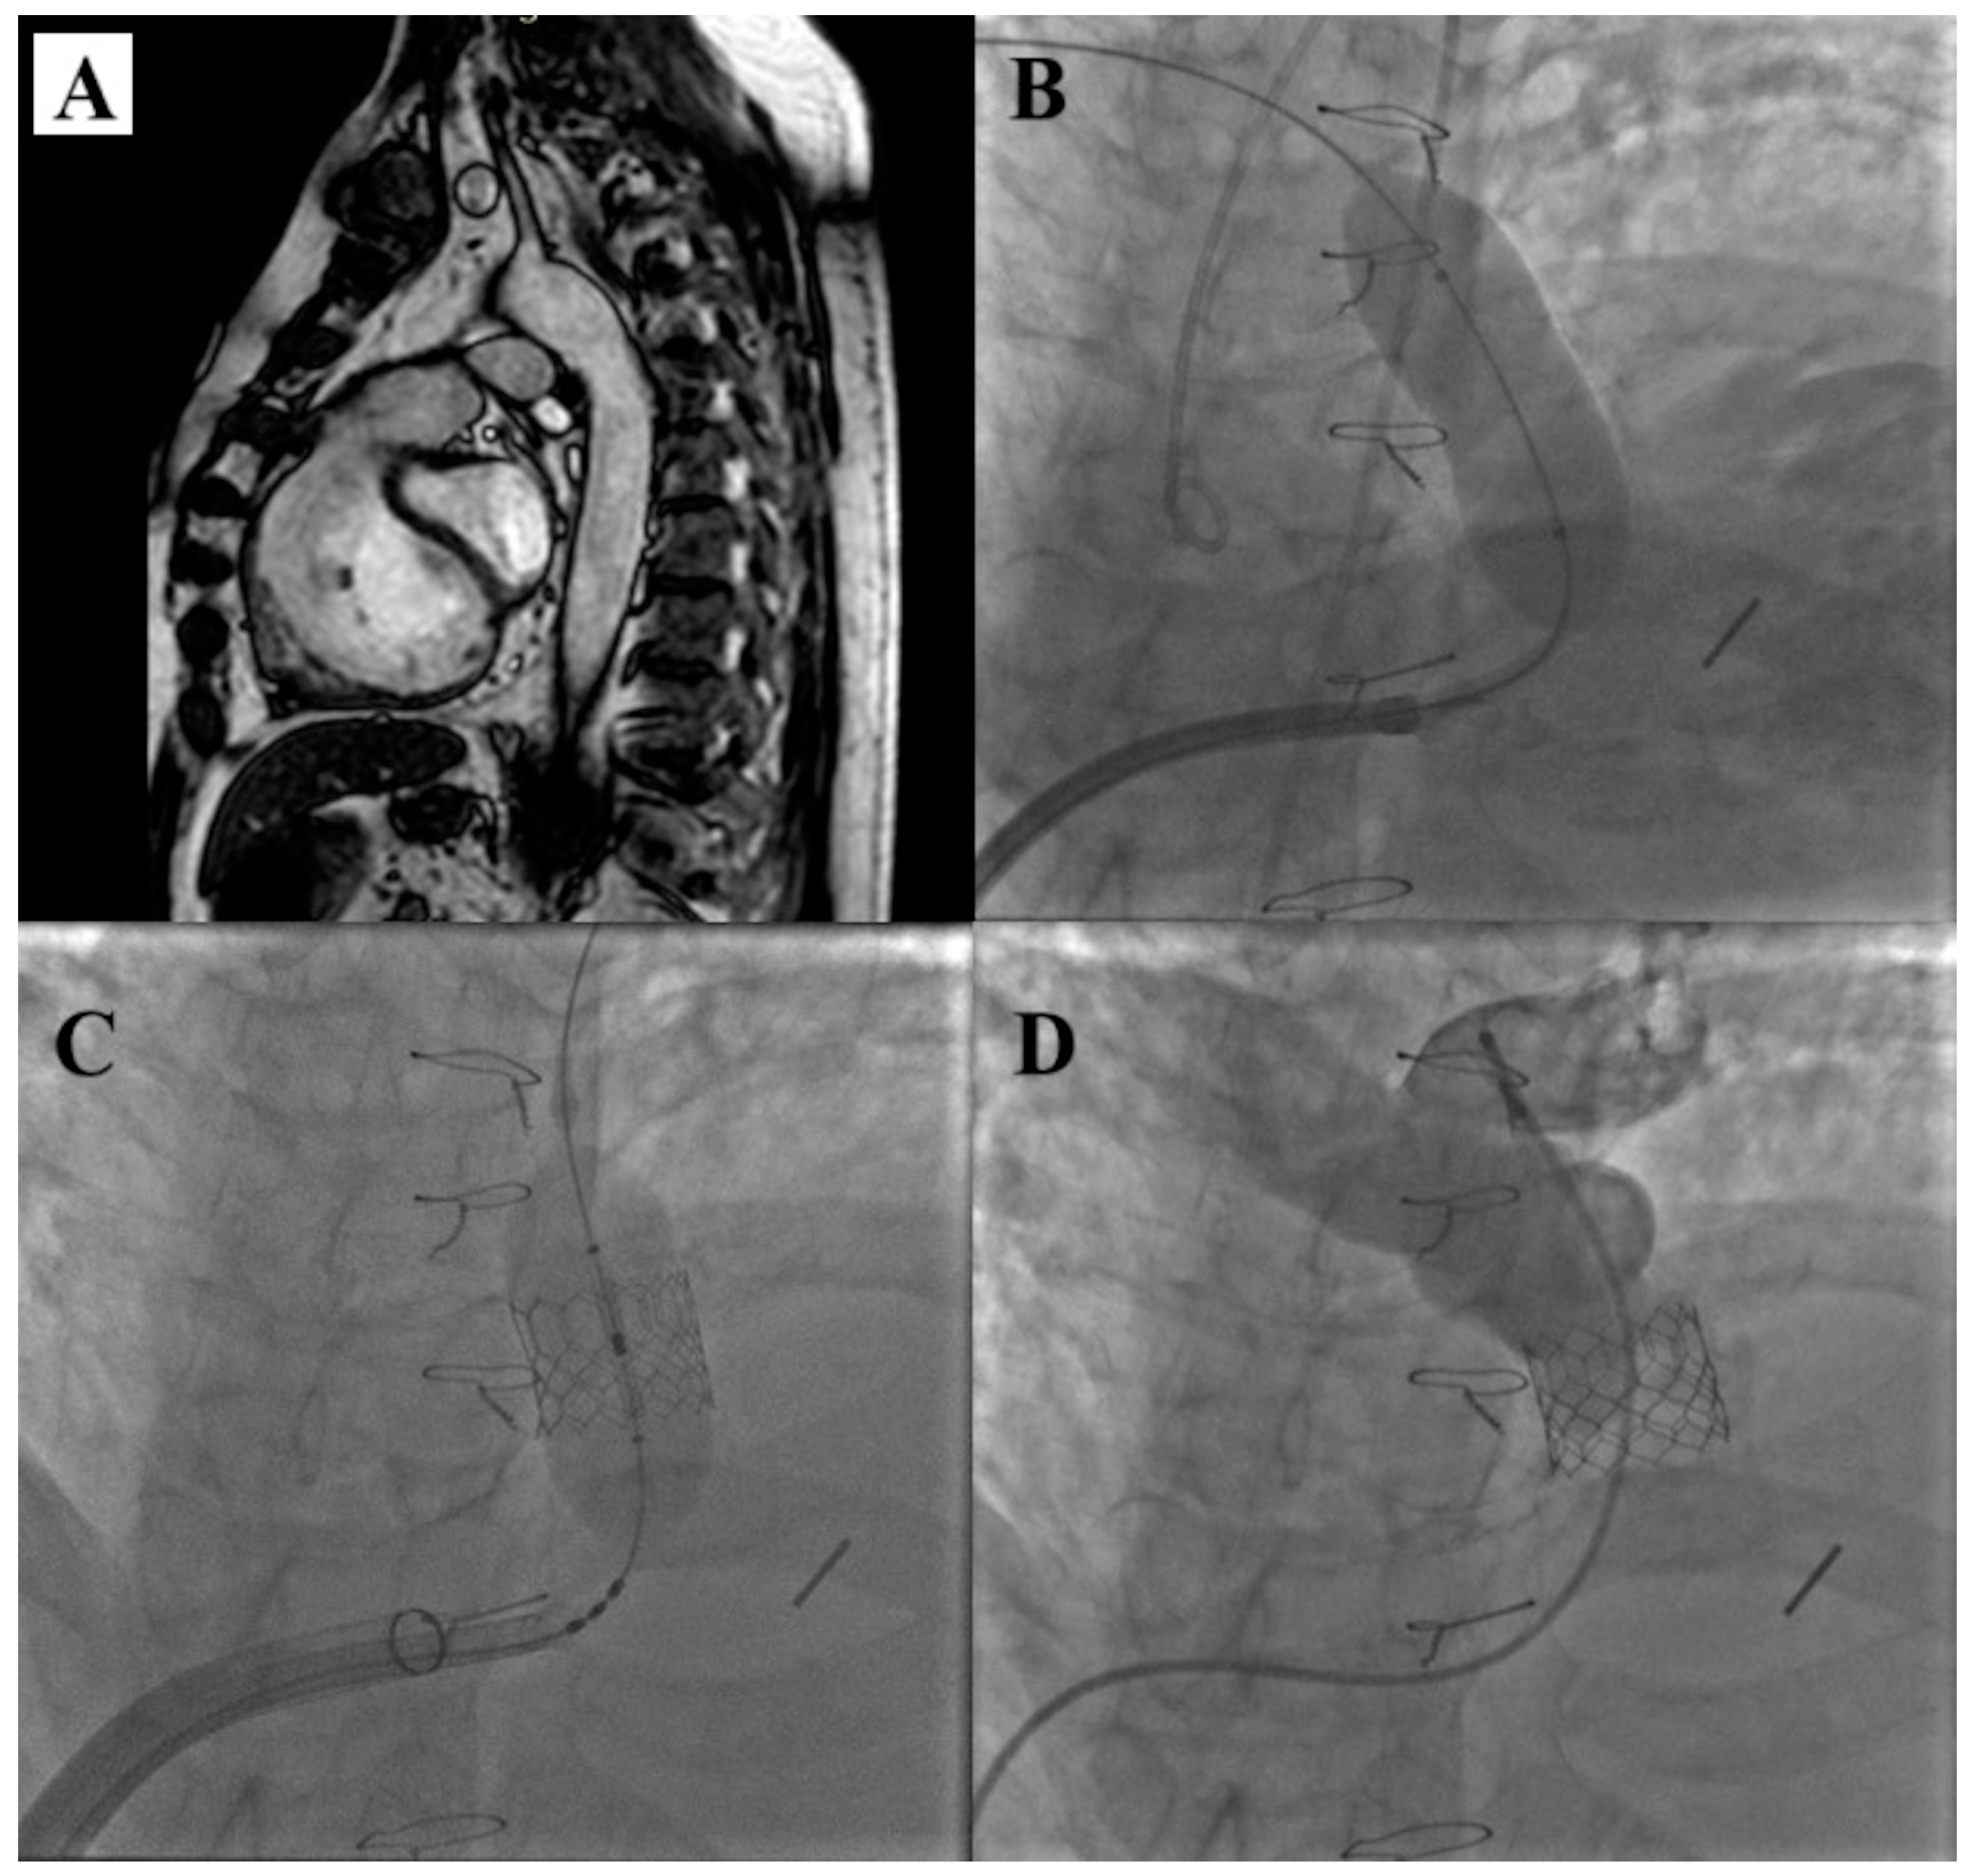

- Zahn, E.M.; Chang, J.C.; Armer, D.; Garg, R. First human implant of the Alterra Adaptive Prestent TM: A new self-expanding device designed to remodel the right ventricular outflow tract. Catheter. Cardiovasc. Interv. 2018, 91, 1125–1129. [Google Scholar] [CrossRef]

- Dimas, V.V.; Babaliaros, V.; Kim, D.; Lim, D.S.; Morgan, G.; Jones, T.K.; Armstrong, A.K.; Berman, D.; Aboulhosn, J.; Mahadevan, V.S.; et al. Multicenter Pivotal Study of the Alterra Adaptive Prestent for the Treatment of Pulmonary Regurgitation. JACC Cardiovasc. Interv. 2024, 17, 2287–2297. [Google Scholar] [CrossRef]